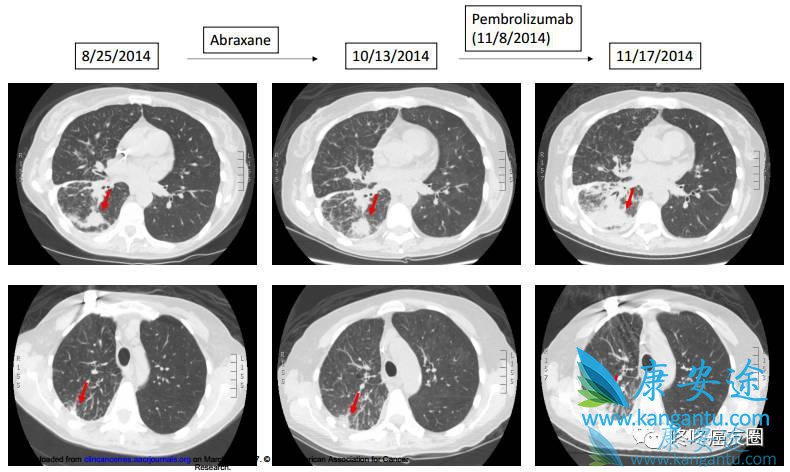

50岁,肺腺癌,基因检测显示MDM2扩增,伴随KIF5B-RET融合,使用白紫化疗无效,之后改用PD-1抗体Keytruda,用药9天之后,患者的状态急剧恶化,严重的乏力。医生无奈,只能进行CT检查,发现一个月之后患者的肿瘤增大了很多(原文的描述是:9天时间增大1.3倍)。